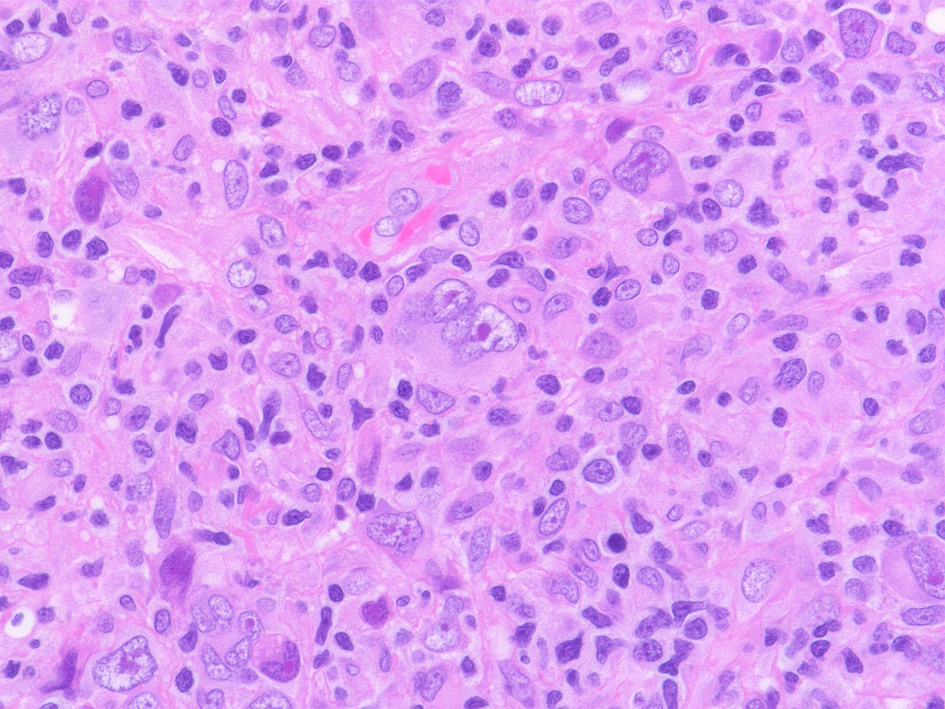

48歳男性 頚部リンパ節 Hodgkin lymphoma, mixed cellular type.

Hodgkin cell(mononuclear RS cell, 中心性核小体が小型リンパ球の核ほどに大きくめだつ), Reed-Sternberg cells(二核細胞)

左;腫瘍細胞のクラスター, 右: mummy cell-ミイラ細胞